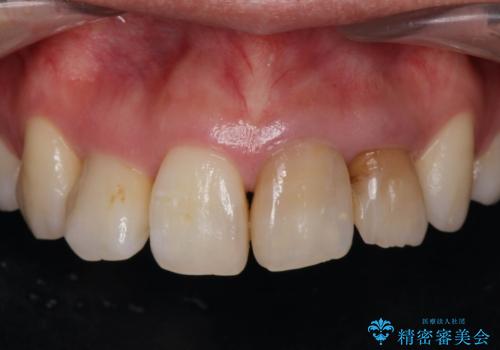

- 神経の死んでしまっている前歯の変色の改善を求めて来院されました。

根管治療をしたのち時間が経過して変色が目立つ歯と、レジン充填が複数箇所に及んでいる歯も同時にオールセラミック治療を行っていくこととなりました。